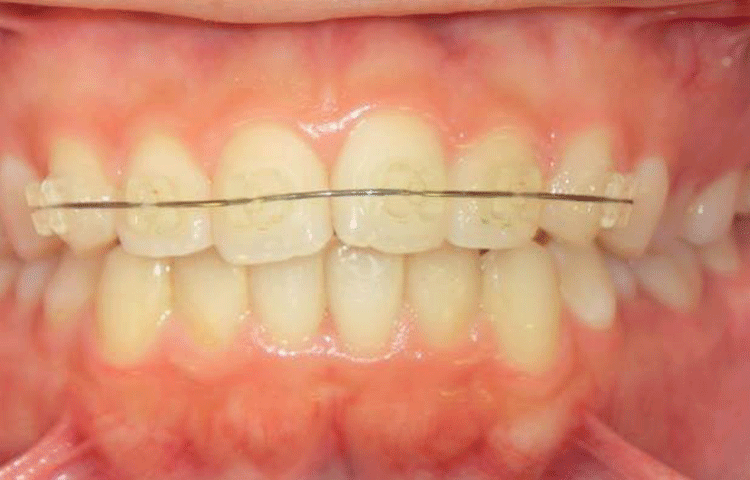

ワイヤー矯正

ワイヤー矯正は歯に「ブラケット」という装置を取り付け、そこにワイヤーを通して少しずつ歯を動かしていく最もスタンダードな矯正法です。

治療中の矯正装置が目立つのがイヤ。そんな方にはマウスピース矯正をご提案します。

透明なマウスピースを装着するだけの簡単さで、目立たず取り外しができることから、女性を中心に当院でも人気が高まっています。